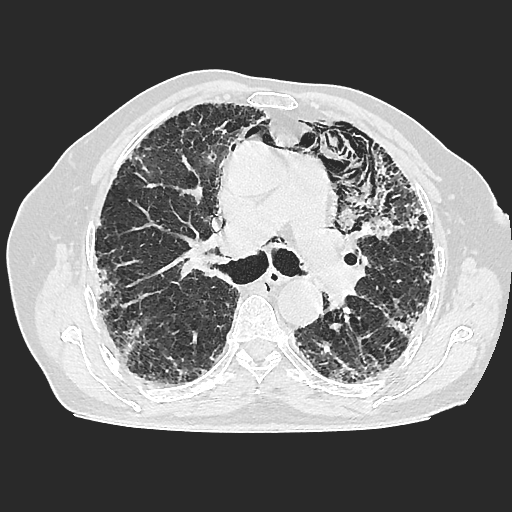

El parénquima pulmonar izquierdo muestra un infiltrado intersticial difuso que causa engrosamiento del septum axial, además del fenómeno de bronquiectasias quísticas se observan pequeñas bulas enfisematosas de localización subpleural que compromete ambas bases pulmonares.

Se observan imágenes de vidrio despulido en todo el lóbulo inferior izquierdo, el cual compromete los segmentos de la língula del segmento superior y medio

El parénquima pulmonar derecho muestra infiltrado intersticial en imagen de vidrio despulido con evidencia de lesiones subpleurales que representan bullas enfisematosas de diferentes tamaños.

Al utilizar un contraste Minip, se observan bronquiectasias cilíndricas en el extremo del lóbulo superior derecho, observándose un patrón de panal de abeja situada en la región apical del lóbulo superior izquierdo.

Bronquiectasias cilíndricas, bullas enfisematosas basales bilaterales